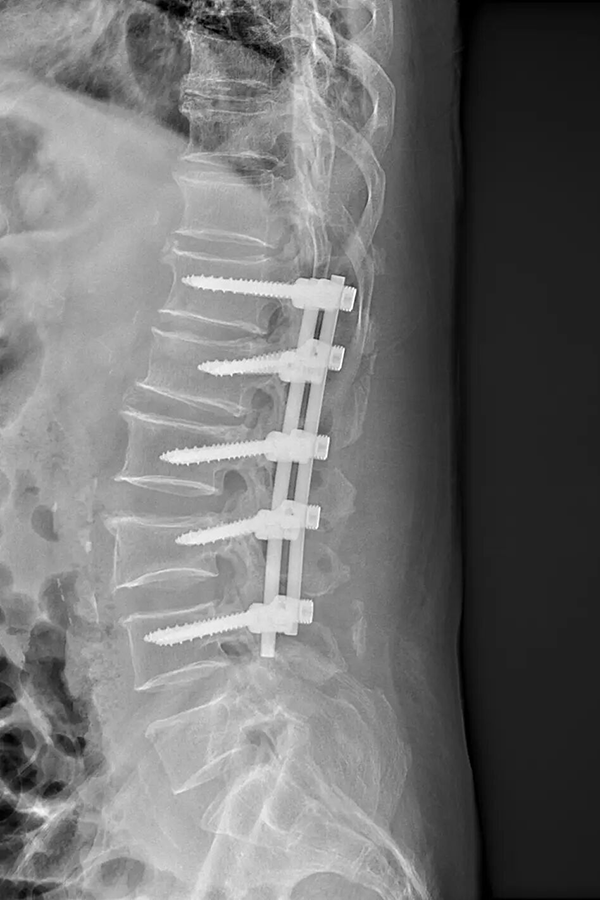

手术过程中,脊柱外科医疗团队凭借丰富的临床经验和精准的操作技巧,通过微创切口,沿肌肉自然间隙精准分离,避开重要神经和血管,顺利暴露入钉点。在C臂机的引导下,医生精准定位、逐一枚入十枚螺钉,术中创伤小,出血量极少。

从术前对老人身体机能的全面评估、量身定制个性化手术方案,到术中多学科团队精准协作、精细操作,再到术后一周即可顺利下地活动,这场 “十钉亦微创” 的手术,不仅成功治愈了患者的多节段脊柱爆裂性骨折,更以精准微创的技术为高龄患者筑牢生命安全防线。手术打破了 “高龄多节段骨折难治愈、术后恢复慢” 的传统认知,这不仅是脊柱微创技术实力的有力彰显,更是医者仁心的生动实践。

➜该入路可以更清晰地呈现骨折区域与解剖构造,帮助医生精准植入螺钉、顺利完成穿棒固定,完美攻克了多节段骨折传统微创术式穿棒难度大、复位效果差的痛点,在保障手术效果的同时,最大程度降低手术创伤。

➜凭借精准的撑开复位技术,这项术式还可以将突入椎管内的骨块复位,彻底解除脊髓神经受压问题,实现治疗与功能恢复兼顾,在保障手术安全性的同时,收获理想治疗效果,已然成为高龄多节段爆裂性骨折患者的首选治疗方案。